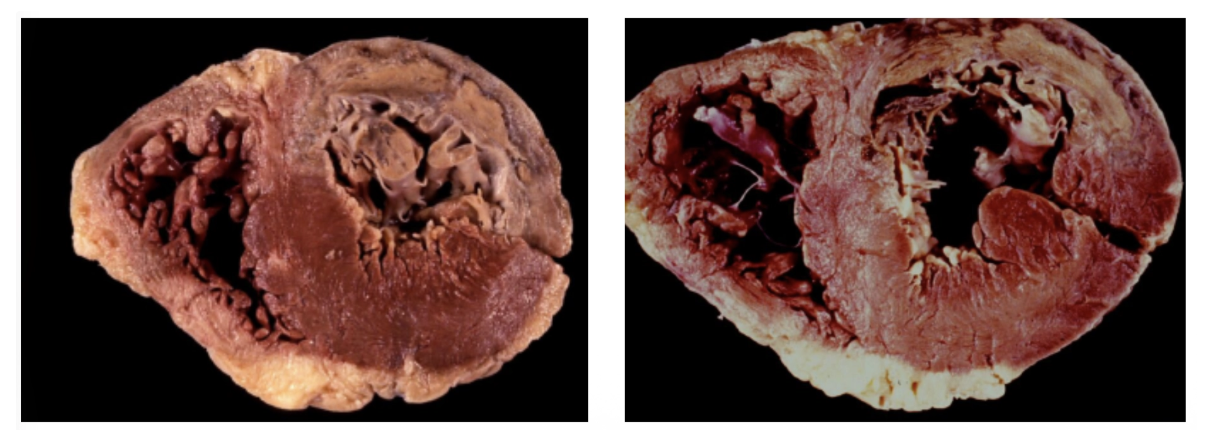

Cardiopatía isquémica crónica